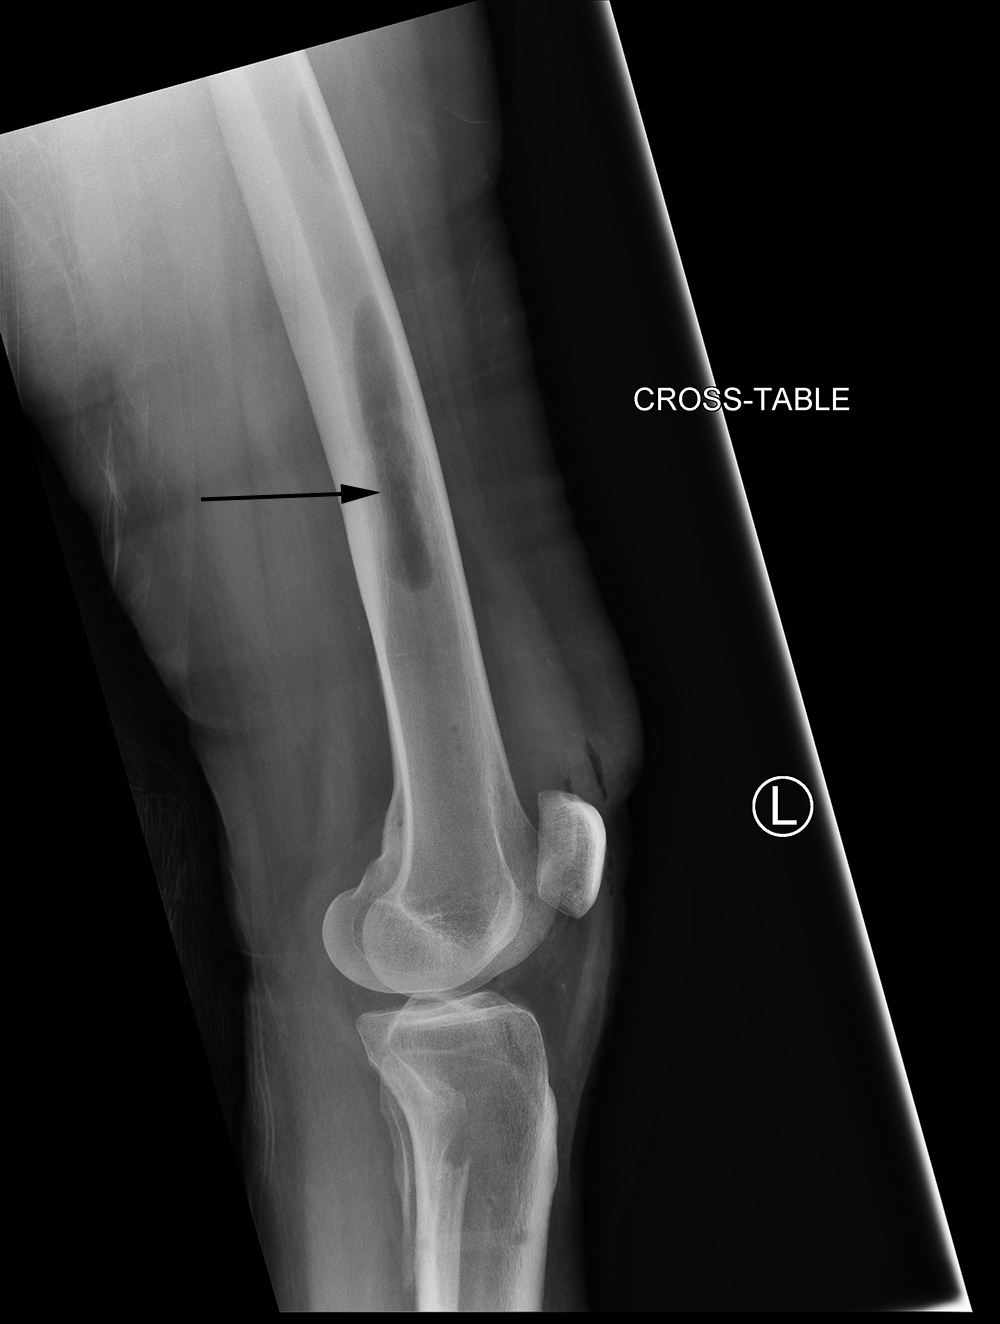

41 year-old woman with left distal tibial pilon fracture with considerable bone loss. Bone graft harvesting to replace the lost bone was done from the left femur using a DePuy Synthes RIA intramedullary bone graft harvest system. The left two images show the reamer in the left femur. The right two images show postoperative gas (arrow) from the bone harvest site. Courtesy Kellon Hansen, MD.